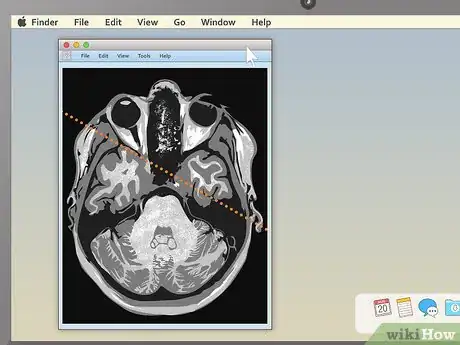

5. 5

Drag the section-cut line to view new parts of the study. Dragging the section-cut line to a different part of the image allows you to "move around" your MRI images. The image should change your view to the new area automatically.

• For example, if you're viewing a sagittal image of your spine along with a cross section of one of your vertebrae, moving the section-cut line may allow you to cycle up and down through the various vertebrae above and below it. This can be useful for locating problems like herniated discs.